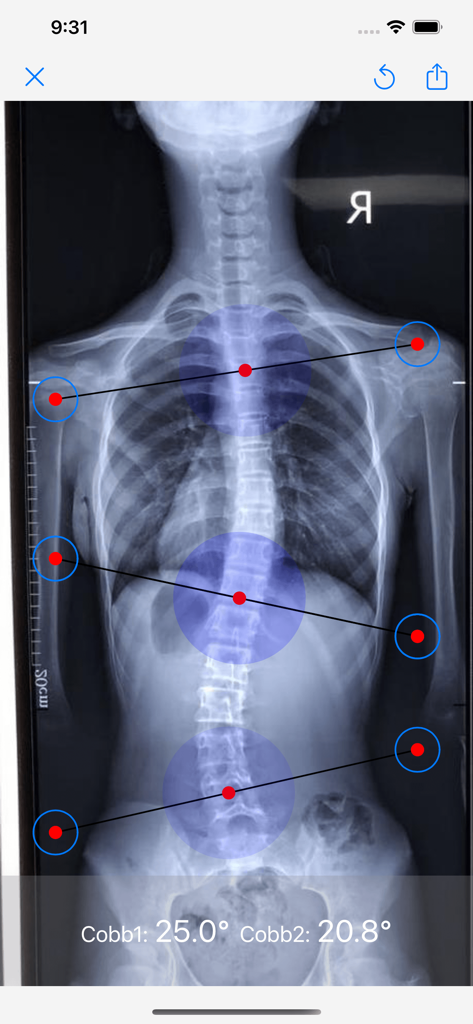

脊柱侧弯cobb角测量 - Spinal X-ray with automated Cobb angle measurements for scoliosis diagnosis

Spinal X-ray with automated Cobb angle measurements for scoliosis diagnosis

Instantly calculate Cobb angles from full-spine X-rays using intelligent algorithms with over 95% accuracy for rapid clinical assessments.

Maintain complete control with the ability to manually adjust end-vertebrae lines, ensuring measurements meet your exact standards for reliability.

本软件可用于自动智能测量脊柱侧弯cobb角,只要上传合格的全脊柱正位X光片,即可自动得出cobb角。 本软件面向医生或有一定脊柱侧弯专业知识的用户。使用方法如下: 1、上传影像图片建议截取全脊柱X线正位片,尽量避免折痕,图像倾斜等。 2、本程序cobb角测量准确率>95%,当弯弧较短、有不规则多弯、顶椎在胸5以上或腰3以下、旋转度较大、上传影像图片质量不高(如图片倾斜,有划线,折痕等)时可能产生一定小误差。 3、用户可测量3次取平均值以提高正确率,测量结果仅供用户参考,具体含义解读需结合专业人员解读。 4、自动测量后,亦可手动拖动端椎线进行cobb角度校正 注意:本软件非医疗软件,测量结果仅供参考。如需诊断或医疗,请咨询专业医师。